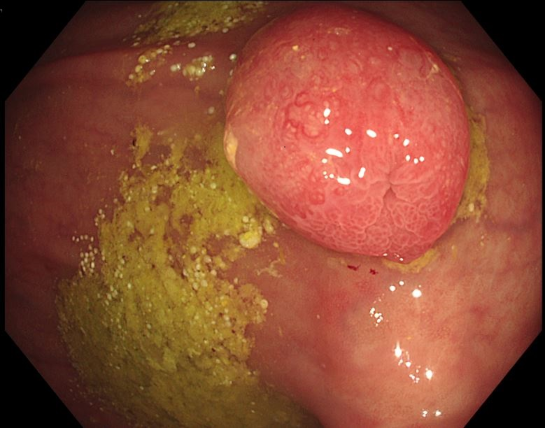

Methode: Wir berichten den Fall einer 85-jährigen Patientin, die sich bei Flankenschmerzen notfallmäßig vorstellte. Am Morgen zuvor erfolgte bei rezidivierenden Subileus-Ereignissen eine Koloskopie mit Polypabtragung und Clipping im Sigma.

Ergebnisse: In der Akutdiagnostik zeigte sich sonographisch eine Harntransportstörung III° bds., laborchemisch ein akutes Nierenversagen mit einem Kreatinin von 2,3 mg/dl sowie eine beginnende Infektkonstellation (Leukozyten von 12,95 Tsd/µl, CRP von 3,7 mg/dl). Das im Anschluss durchgeführte CT zeigte eine Hydronephrose beidseits sowie ektatische Ureteren bis zur Insertionsstelle im Sigma, wobei die Clips in unmittelbarer Nachbarschaft lokalisiert schienen. Es erfolgte die Anlage von Nierenfistel-Kathetern (NFK) bds. sowie die koloskopische Entfernung der Clips. Laborchemisch normalisierten sich die Retentionsparameter. Nach 3 Wochen objektivierte eine antegrade Darstellung über die NFKs rechts einen regelrechten Abfluss, während sich links ein Kontrastmittelabbruch im Bereich der Einmündung des Ureters in das Sigma zeigte. Somit verblieb der NFK links als Dauerversorgung. Aufgrund des Patientenalters entschieden wir uns gegen eine Neueinpflanzung oder anderweitige Harnableitung.

Schlussfolgerung: Das Vorliegen einer US ist ein seltener Situs im klinischen Alltag. Daraus ergibt sich, dass diese Rekonstruktionstechnik in anderen Disziplinen oftmals nicht mehr ausreichend Beachtung findet. Da die Harnleitermündungen als polypoide Veränderungen im Rahmen endoskopischer Interventionen missinterpretiert werden können, entstehen zusätzliche Risiken. In diesem Fall hat dies zu einem iatrogenen Verschluss der Harnleitermündungen und im weiteren Verlauf zu einer Dauerableitung der linken Niere mittels NFK geführt. Bei erhöhtem Risiko für kolorektale Polypen und malignen Veränderungen im Bereich der Anastomose nach US ist eine Abtragung nur bei hochgradig malignitätsverdächtigen Läsionen sowie einer interdisziplinären Zusammenarbeit sinnvoll, um o.g. Komplikationen zu vermeiden.

Abbildung 1 [Abb. 1]